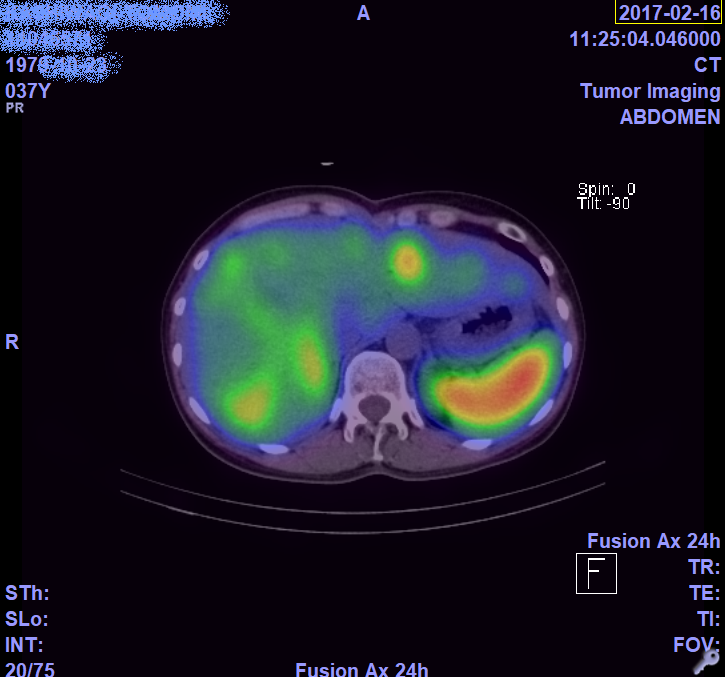

2月のCTとオクトレオスキャンの画像。

これが無治療だと半年で肝不全なっちゃう?肝臓らしいよ。

ちょっと肝臓腫れてるらしいけど、わからないね…

わかるかな?CTは白いやつが全部腫瘍。

オクトレオスキャンは光ってるやつ(二枚目の大きい濃いオレンジは違うよ)

参考にどうぞ。